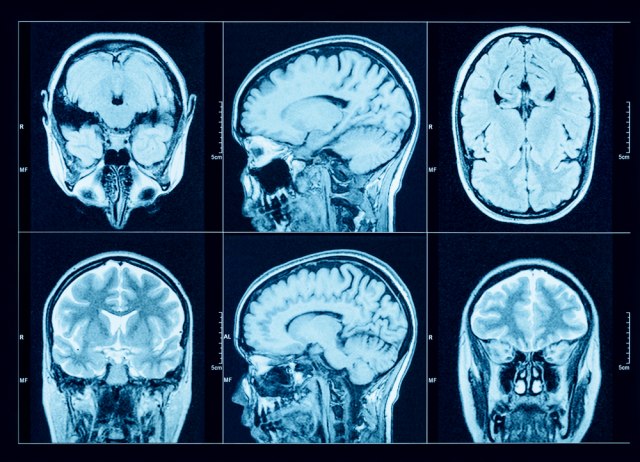

Mentalne posledice kovida: Šta su otkrile autopsije ljudi koji su umrli od koronavirusa

Foto: Triff/ Shutterstock